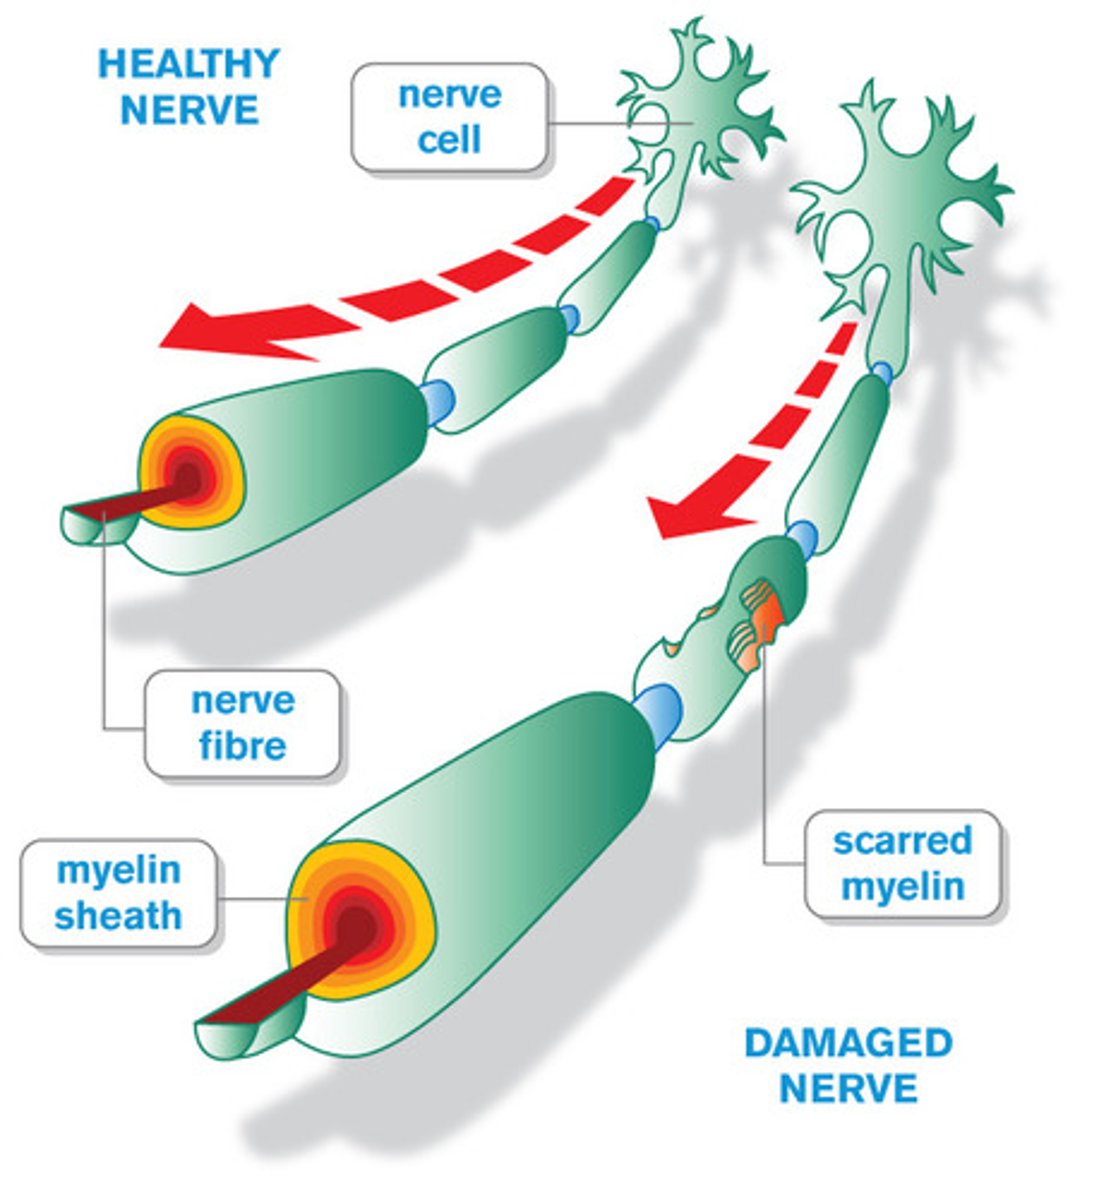

Multiple sclerosis (MS)

a degenerative disease caused by destruction of the myelin sheath on neurons in the CNS characterized by sclerotic patches along the brain and spinal cord

Glial cells

play a role in the formation of myelin and the blood-brain barrier, response to injury, removal of debris, and enhancing learning and memory